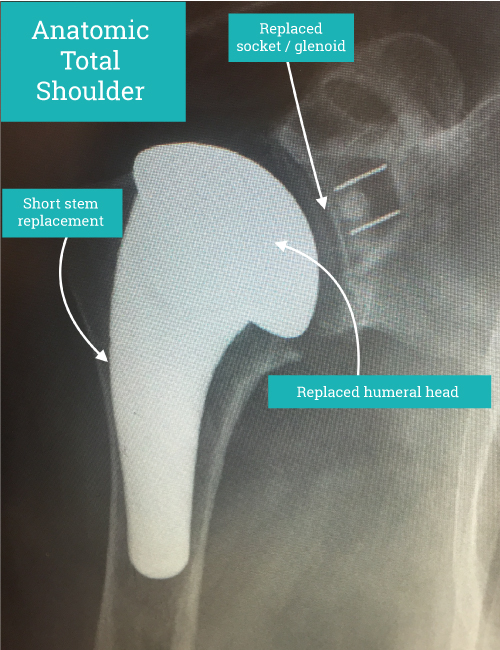

Anatomic Shoulder Replacement